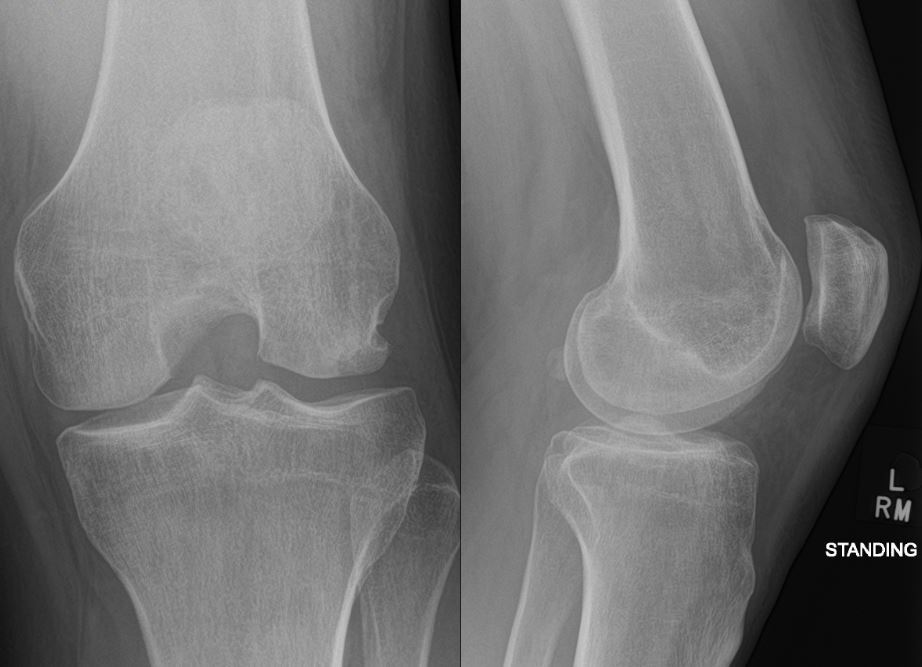

Post-operatively the patient was allowed to mobilize non weight bearing with crutches on the affected side for 6 weeks. His knee was placed in a hinged knee brace locked in extension for the first 2 weeks followed by increase in range of motion (ROM) by 30 degrees at 2 weekly intervals. At 8 weeks post operatively, he was mobilized out of the brace and allowed weight bearing as tolerated and started physiotherapy rehabilitation program. At 6 months follow up, the knee was found to exhibit a full range of motion. The Patella was tracking centrally, and the patella apprehension test was negative. The radiographs confirmed healing of the OCF (Figure 9). The patient has not reported any issues since his surgery, 18 months ago.

Figure 9 AP & Lateral of Knee radiographs at 12-month follow up.